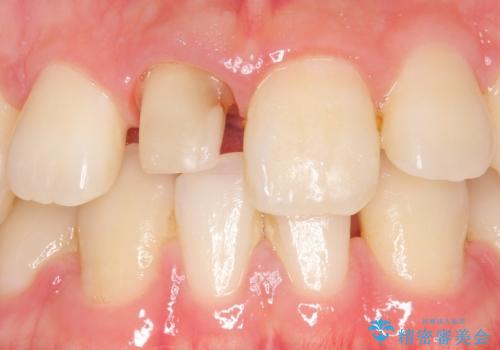

- 右上1番目の前歯の変色が気になるといらっしゃった方の症例です。

再根管治療後、オールセラミッククラウンによる補綴を行いました。